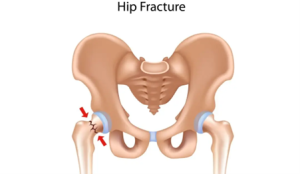

آسیبها و شکستگیها: صدمات شدید مانند شکستگیهای پیچیده و دررفتگیهای مفصل ران که با روشهای معمول قابل درمان نیستند، ممکن است نیاز به تعویض مفصل ران داشته باشند.

عکس شماره ۳: شکستگی مفصل ران